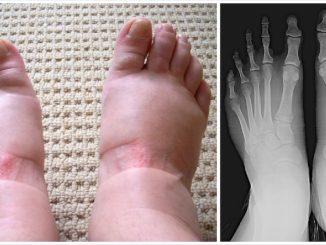

HT17. My feet feel hot and burning when I lie down at night, even though they’re cold to touch. What’s going on?

Late at night, when the house is quiet and your body finally slows down, an unsettling sensation begins. Your feet feel hot, burning, almost as […]